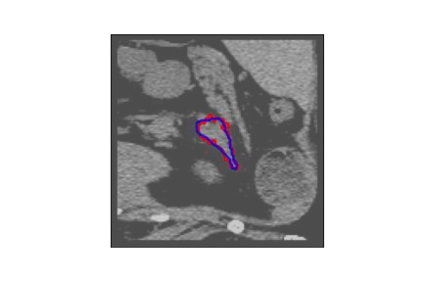

The human annotations are imperfect, especially when produced by junior practitioners. Multi-expert consensus is usually regarded as golden standard, while this annotation protocol is too expensive to implement in many real-world projects. In this study, we propose a method to refine human annotation, named Neural Annotation Refinement (NeAR). It is based on a learnable implicit function, which decodes a latent vector into represented shape. By integrating the appearance as an input of implicit functions, the appearance-aware NeAR fixes the annotation artefacts. Our method is demonstrated on the application of adrenal gland analysis. We first show that the NeAR can repair distorted golden standards on a public adrenal gland segmentation dataset. Besides, we develop a new Adrenal gLand ANalysis (ALAN) dataset with the proposed NeAR, where each case consists of a 3D shape of adrenal gland and its diagnosis label (normal vs. abnormal) assigned by experts. We show that models trained on the shapes repaired by the NeAR can diagnose adrenal glands better than the original ones. The ALAN dataset will be open-source, with 1,594 shapes for adrenal gland diagnosis, which serves as a new benchmark for medical shape analysis. Code and dataset are available at https://github.com/M3DV/NeAR.